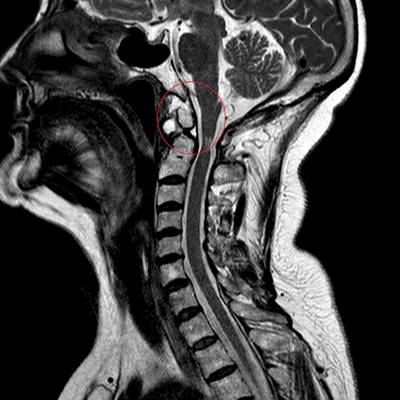

МРТ: перелом зубовидного отростка второго шейного позвонка (сагиттальная плоскость, Т2 ВИ)

Чтобы открыть МР-снимки, понадобится специальная программа (DICOM Viewer, RadiAnt и пр.), скачать которые можно в интернете. Иногда на электронном носителе есть файл для установки приложения: запустите его, следуя инструкции.